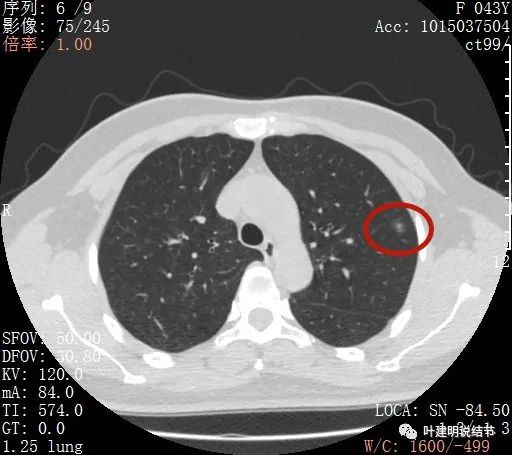

上图示病灶内部有高密度点状成分(粉色箭头所指)

同样示内部点状高密度,瘤肺边界清,密度显乱

上图显示混合磨玻璃结节,中间点状高密度区域,边上有微小血管征

上图示病灶边缘磨玻璃成分有的区域密度过低(绿色箭头),事后回头来看,磨玻璃部分的密度过低,不容易是浸润性腺癌,而更符合原位腺癌

上图示瘤肺边界处显模糊(砖色箭头),病灶内部仍是有偏高密度的点状成分

上图层面也显示病灶边缘欠清,有些模糊,虽总体轮廓还是比较清晰